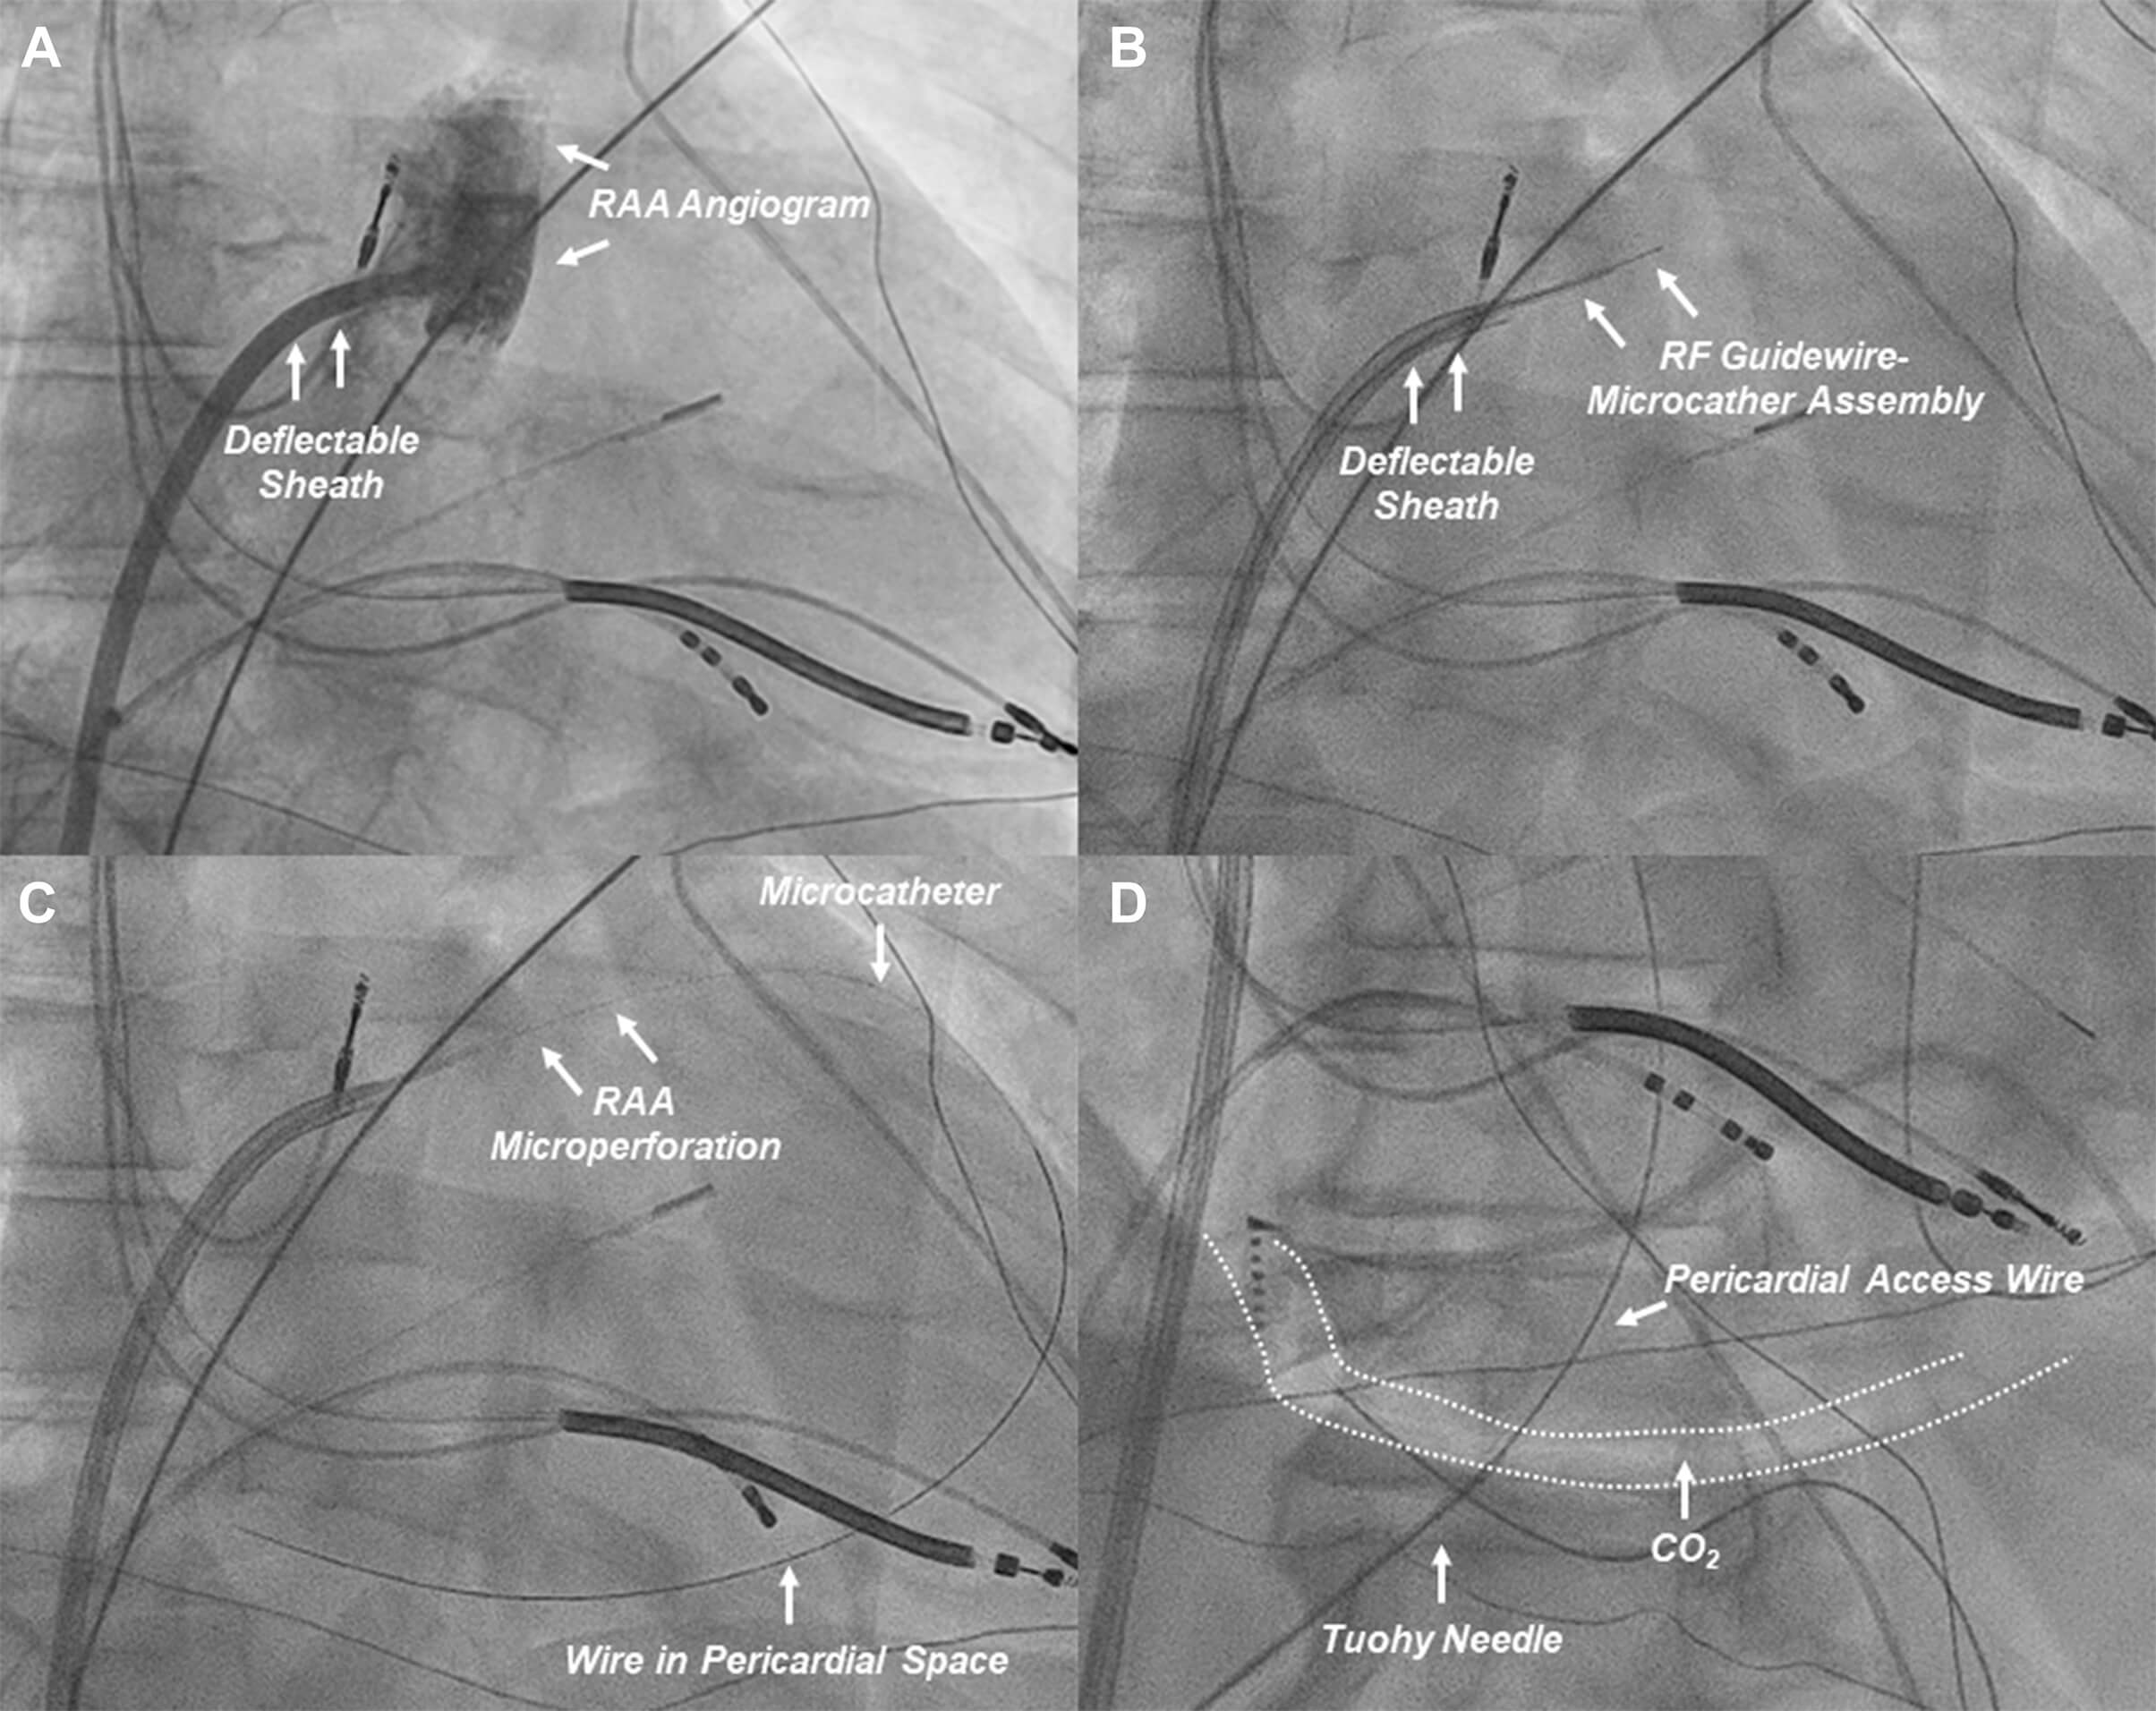

Fig. 8.

Procedural workflow of RAA perforation for CO2 insufflation. (A) An RAA angiogram (right anterior oblique projection) is obtained from a deflectable sheath positioned at the base of the RAA. (B) The custom RF guidewire-microcatheter assembly is advanced to obtain contact with the target RAA wall (anterior aspect of the distal third of the RAA). (C) The RAA wall is perforated to advance the wire and microcatheter to the pericardial space for CO2 insufflation. (D) After CO2 insufflation, subxiphoid anterior pericardial access is obtained. CO2, carbon dioxide; RAA, right atrial appendage; RF, radiofrequency. These figures were modified from the original figure of Santangeli et al. [21].